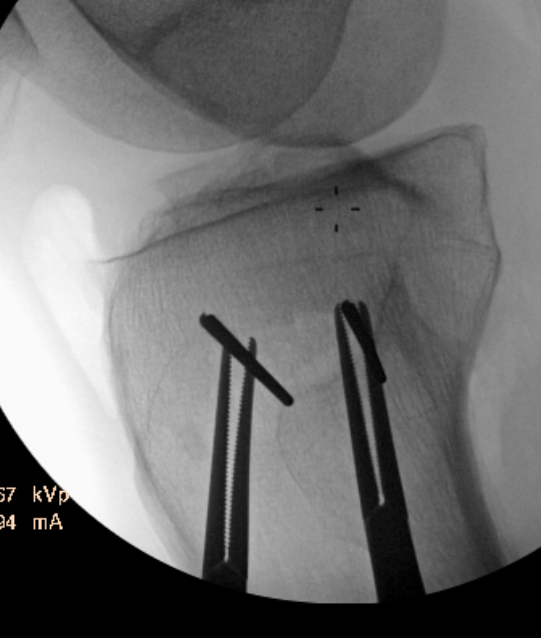

Guide pins for osteotomy and checking posterior slope

Osteotomy to within 1cm of the lateral cortex

Consider lateral hinge 2 mm K wire

- 10 mm from lateral cortex

- distal to proximal